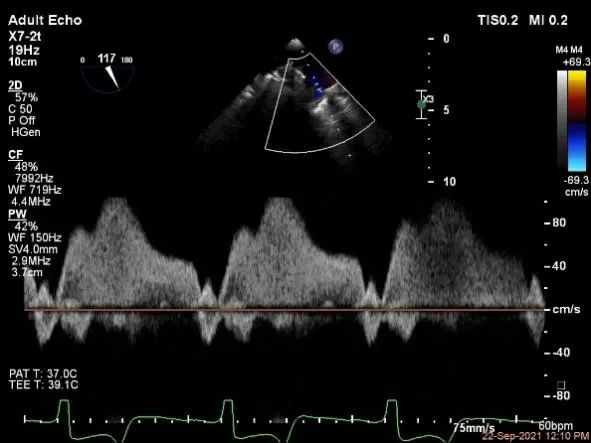

麻醉状态下左肺静脉血流频谱

肺静脉血流频谱恢复正常

麻醉状态下肺静脉血流频谱